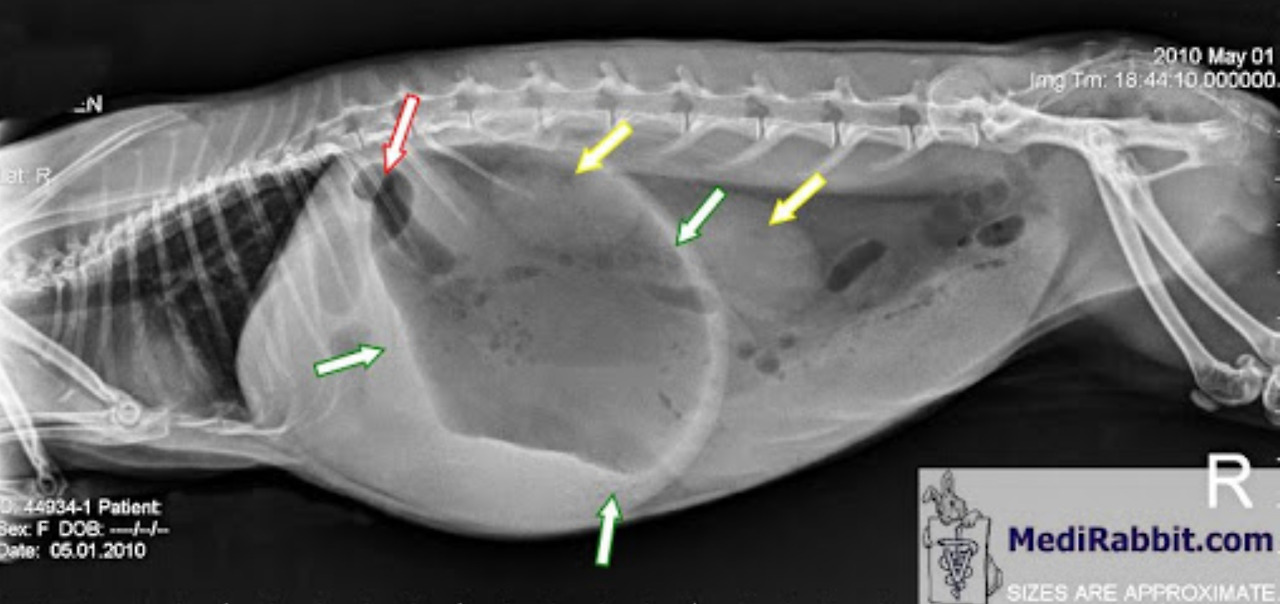

토끼나 소와 같은 반추동물은 고창증(Bloat)이라는 질병이 있습니다. 고창증이란 발효성 사료를 섭취하여 생성된 과량의 가스로 인해 위가 과도하게 팽창하여 심한 복통이나 호흡을 곤란해하는 질병입니다. 발효성 사료에는 부패한 사료, 수분함량이 많은 콩과 식물(견과류) 등이 있습니다. 마이멜로디가 좋아하는 아몬드 케이크에는 견과류인 아몬드가 들어가 있는데 아몬드를 아주 소량으로 먹으면 괜찮겠지만 사람이 먹는 것만큼 아몬드를 토끼가 먹을 경우 고창증으로 인해 생명이 위험할 수 있습니다. 그래서 마이멜로디는 아몬드 케이크를 끊고 토끼 전용 사료를 먹는 것이 건강에 좋을 것 같습니다.